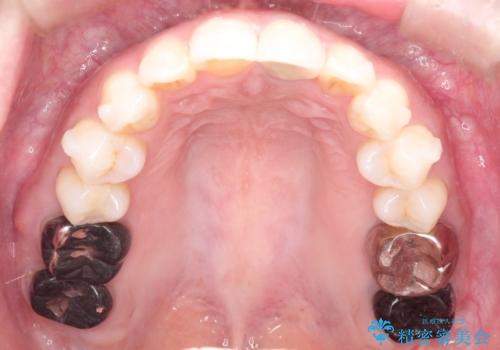

インビザラインによる非抜歯矯正 ガタガタな歯並びを整った歯並びへ

- 上下の全体的ながたつきが気になるとのことで来院されました。

マウスピースでの目立たない矯正を希望されたので、インビザラインでの治療となりました。

全体的に歯と歯の間にわずかに隙間を作り、歯を並べました。